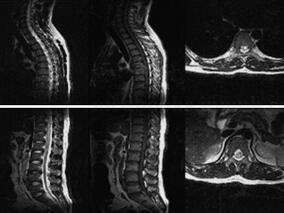

1小时条评论硬脊膜动静脉瘘(SDAVF)是脊髓血管畸形最常见的一种类型,多缓慢起病,但本例患者突发双下肢无力伴小便失禁,如何防止误诊? 硬脊膜动静脉瘘(spinal dural arteriovenous fistula,SDAVF)是脊髓血管畸形最常见的一种类型,约占70%[1]。本文报道一例表现为突然...